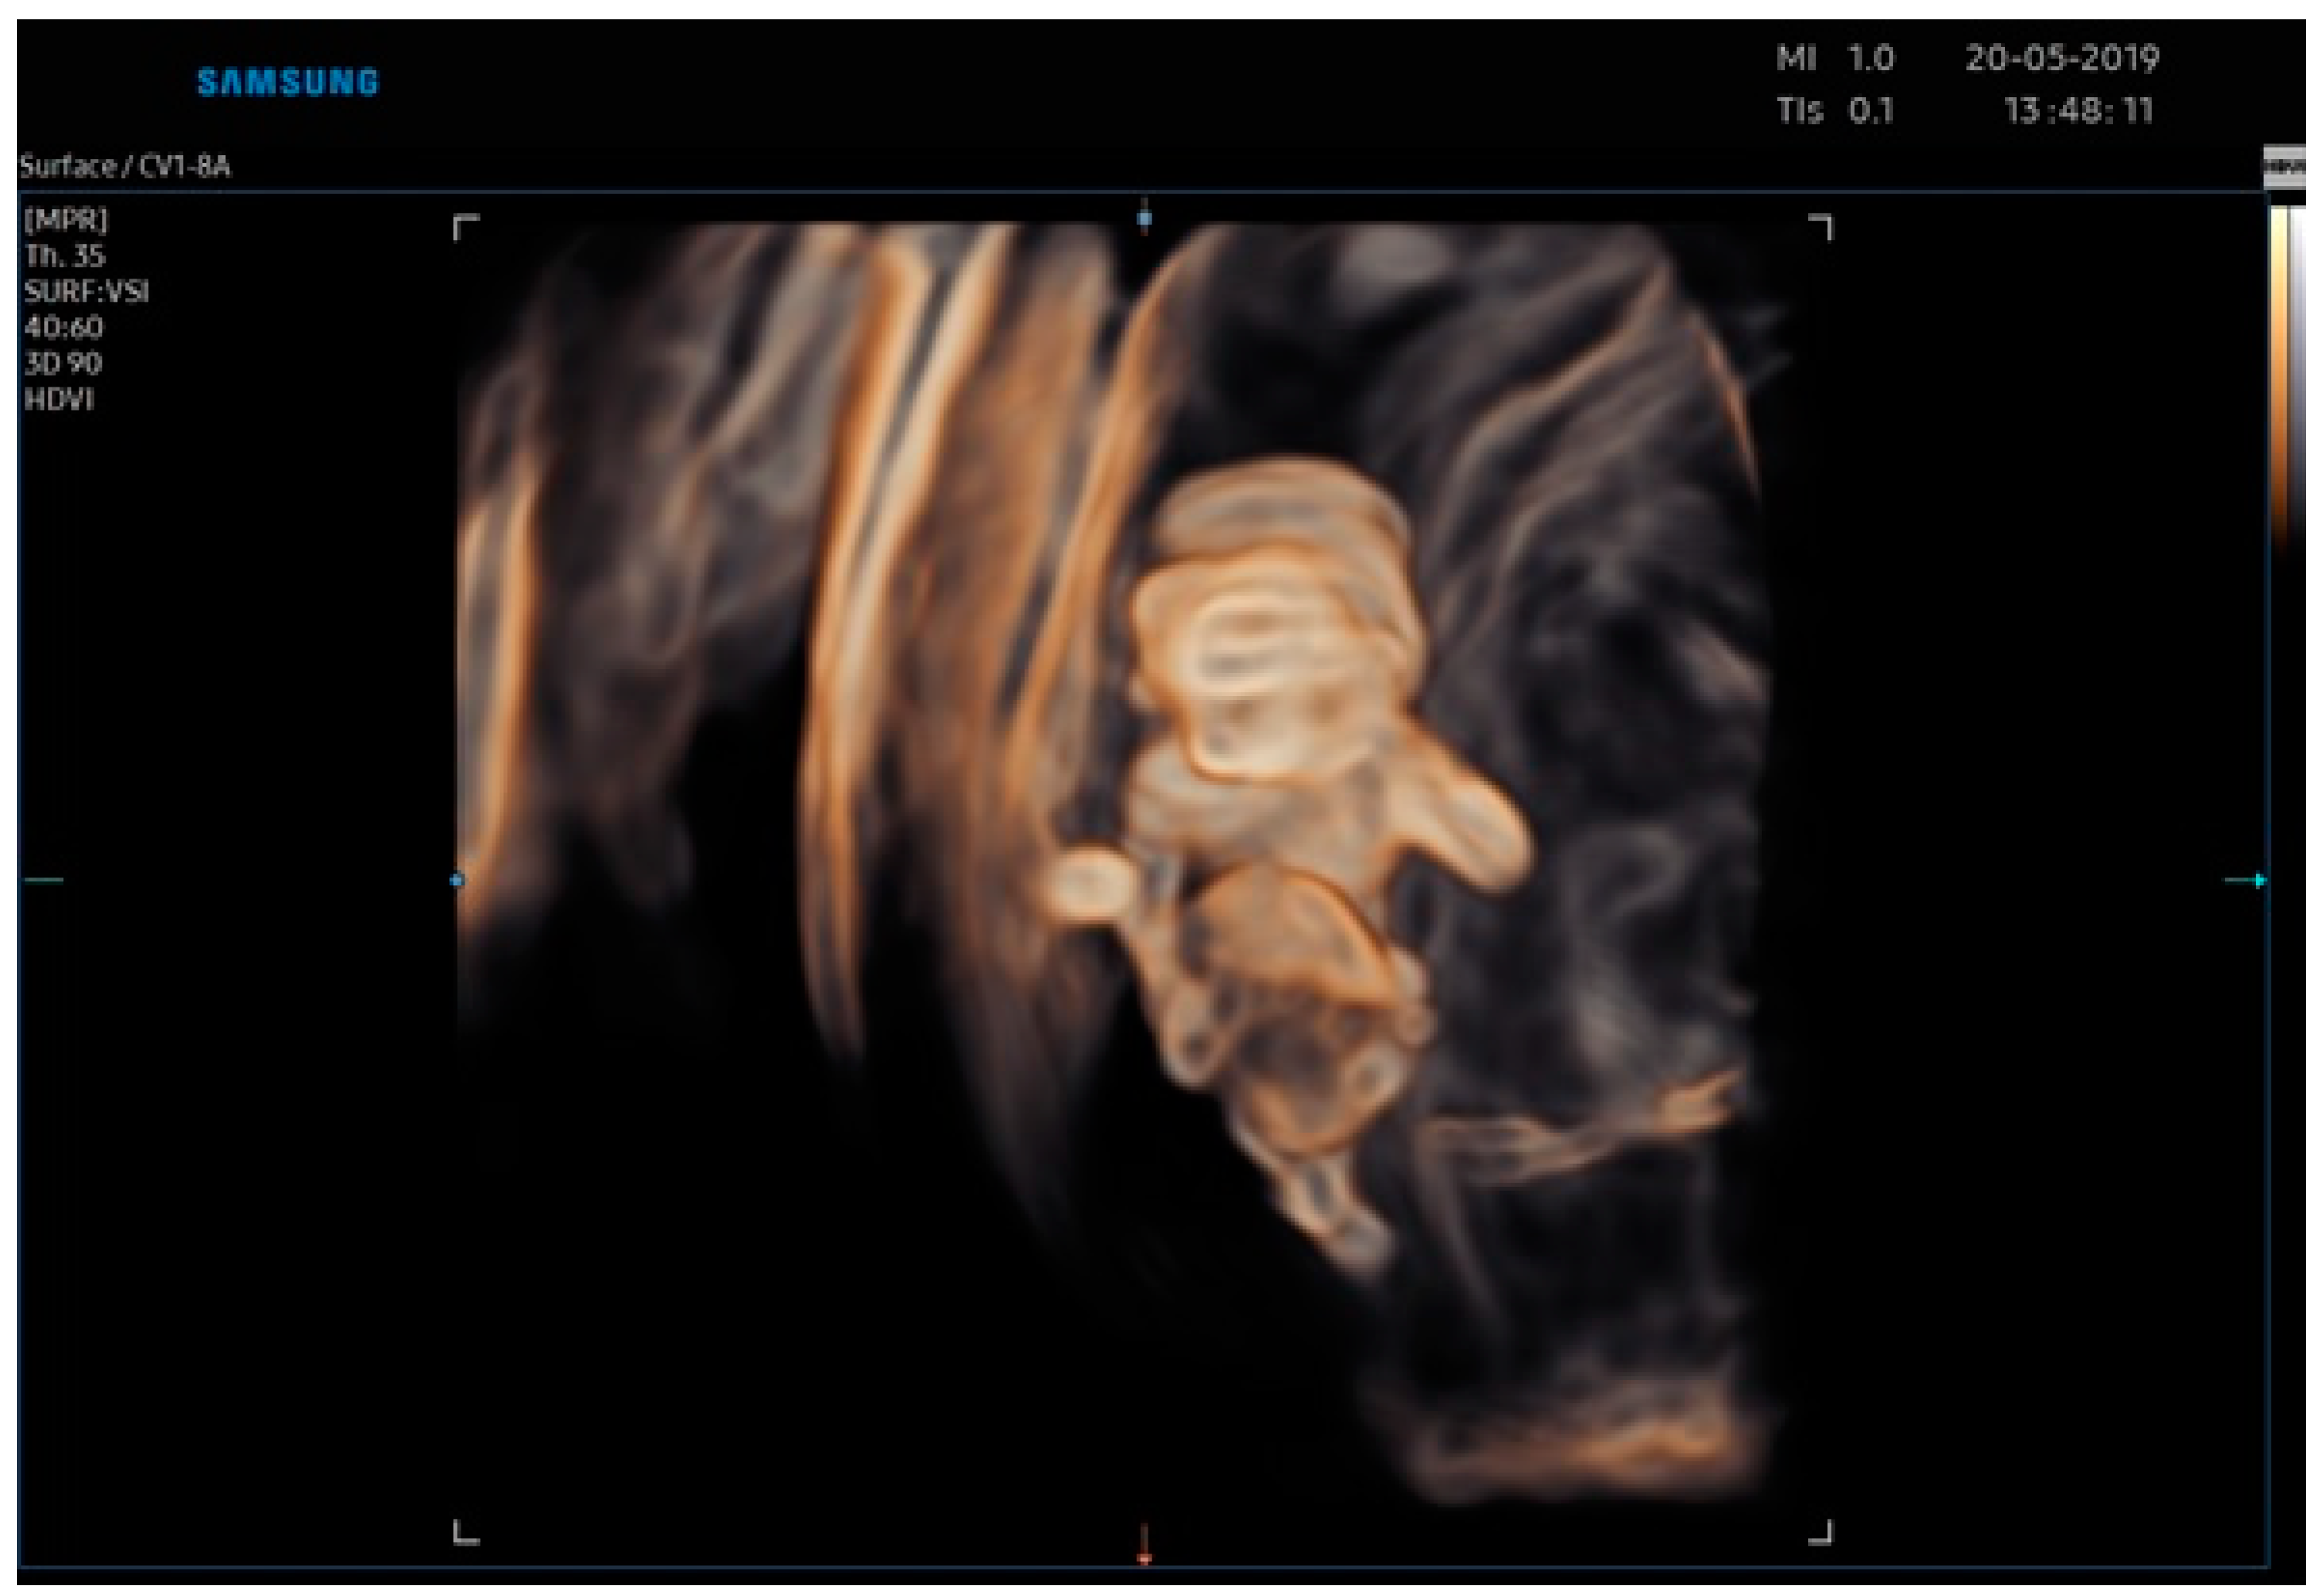

2.2. Case Report 2